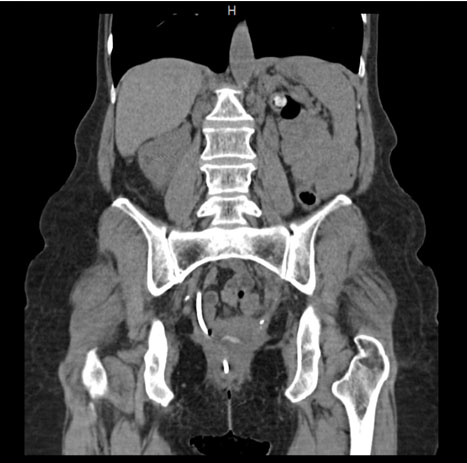

Figure 2: CT scan of the abdomen showing perforation of the urinary bladder by a right ureteral stent and the distal catheter then perforating through the rectum and exiting the anus with the distal pigtail portion of the catheter visualized between the gluteal clefts. There is mild pelvic free fluid and foci of gas in the rectovaginal pouch.

A 55-year-old Caucasian woman presented to the emergency department with complaint of displaced ureteral stent from the anus. She has a history of chronic kidney disease stage IV due to anatomic anomaly of horseshoe kidney with atrophic left kidney as well as vesicovaginal fistula resulting from stage IV cervical cancer treated with high-dose brachytherapy and external beam radiation 10 years ago. Four years after initial treatment with pelvic radiation, she was diagnosed with hydronephrosis secondary to radiation-induced ureteral stricture for which she began to have regular ureteral stent exchanges. The patient presented with the displaced ureteral stent about five years later. The patient said she noticed the end of the stent exiting her anus while she was using the restroom. Urology was consulted which performed cystoscopy to reposition the ureteral stent. The urologist introduced his finger in the rectum to manipulate the stent back into position and was able to visualize the finger on cystoscope which confirmed the diagnosis of colovesical fistula with erosion of the posterior bladder wall (Figure 1 and Figure 2). She was treated with percutaneous nephrostomy catheter placement for ureteral stricture and vesicovaginal fistula as well as a loop colostomy for the colovesical fistula on the same admission. The patient tolerated both procedures well and there were no complications reported.